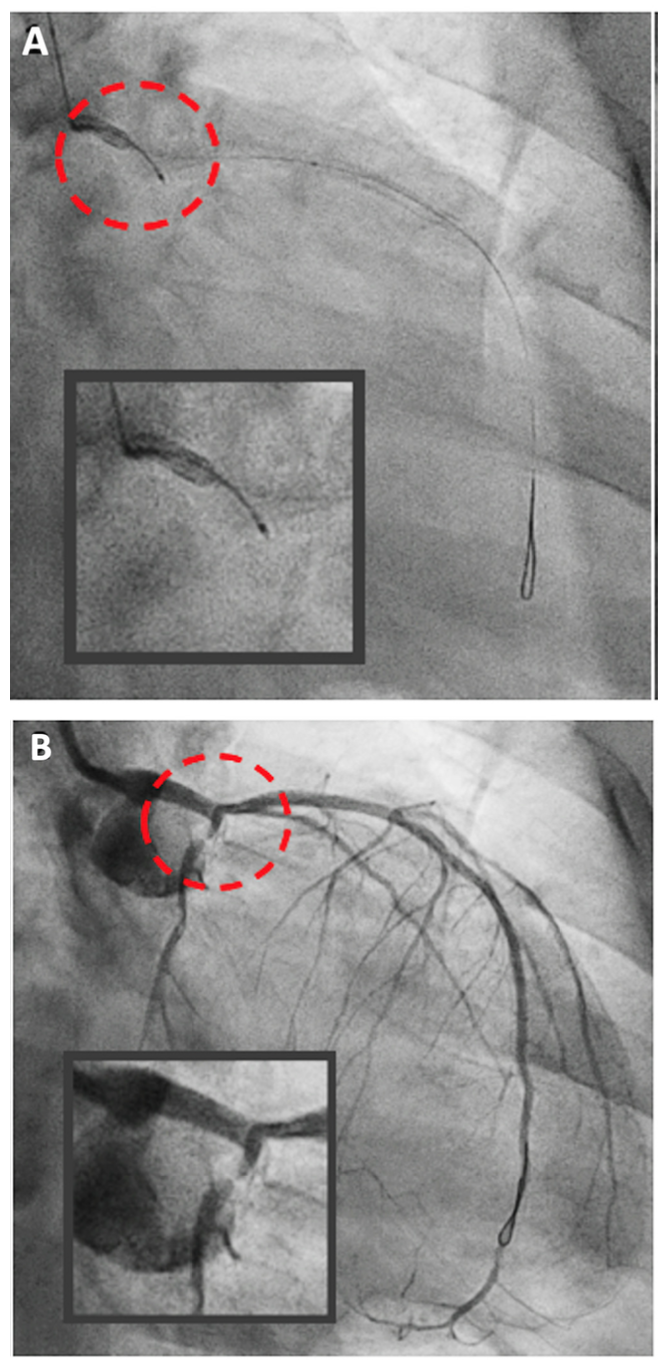

A 53-year-old man was planned for staged percutaneous coronary intervention (PCI) to the left circumflex artery (LCX). He had history of primary PCI at the proximal left anterior descending (LAD) 6 months earlier. Following coronary angiogram (Figure 1A, 1B), it was decided to perform an initial optical coherence tomography (OCT) evaluation. However, during delivery to the LAD, the OCT catheter was railed-off from the guidewire and knocked to the ostial LCX (Figure 2A and Video 1).

Guide-catheter repositioning was performed to have a more coaxial engagement. Subsequently, the OCT catheter was successfully delivered to the distal LAD. The OCT study revealed stenosis with fibrotic plaque at the ostial LAD, eccentric lesion at the distal left main (LM), and intimal tear at the ostial LCX (Figure 3). During OCT evaluation, the patient was experiencing chest pain with unstable hemodynamics. Careful contrast injection revealed dissection at the ostial-proximal part of LCX with compromised antegrade flow (Figure 2B). We performed double-kissing culotte stenting at the left main bifurcation. The patient was then stabilized. The final angiogram and 3-dimensional OCT showed good results (Figure 4).

The purpose of these images is to make the readers aware of the genuine and serious risk of a “railed off” OCT catheter, especially while delivering the catheter at a bifurcation with an eccentric lesion. Meticulous OCT catheter delivery and improvement of the OCT catheter configuration may be considered to avoid this complication.